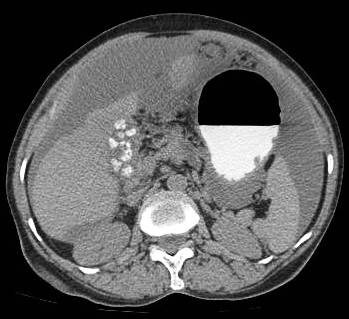

Ascites in advanced gastric cancer swollen stomach cancer. Ascites caused by cancer is called malignant ascites. We'll focus this article on malignant ascites in advanced gastric cancer or swollen stomach cancer. 4 stomach cancer symptoms. Our doctors are here to help you make sense of your stomach cancer.